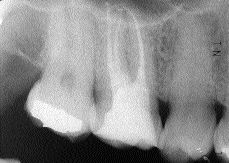

Endodontics: Use of Ophthalmic Dyes in Root Canal Location

FIGURE 27--Immediate postoperative radiograph. Mb and Mb2 join in the coronal third to exit as one canal.

The relationship between uninstrumented root canals and endodontic treatment failure has been studied extensively. Locating all the canals, then subsequently shaping and cleaning them in their entirety has shown to be essential for predictable clinical and biological success.1-4 High visual magnification and fibre optic illumination incorporated in the surgical operating microscope (SOM) has revolutionized endodontic … Read more